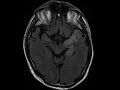

HSV Encephalitis

In this case we see FLAIR hyperintensity, patchy enhancement, and restricted diffusion in the left mesial temporal lobe in a patient who presented with acute onset fevers and altered mental status. These are classic findings for HSV encephalitis, which was confirmed with PCR.